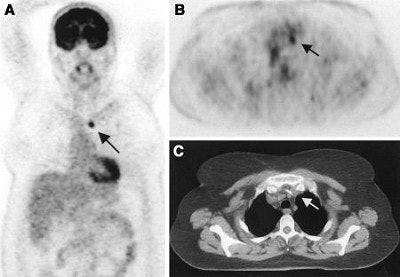

| A 50-year-old woman with lung cancer of right lower lobe. Before FDG-PET, primary curative radiotherapy was planned. Coronal (A) and transverse (B) scans show previously unknown contralateral mediastinal lymph node metastasis (arrow). Lymph node metastasis is not seen primarily on CT scan (C). Radiotherapy volume was increased. Image and caption courtesy of Dr. Elena Dizendorf and the Journal of Nuclear of Medicine. |